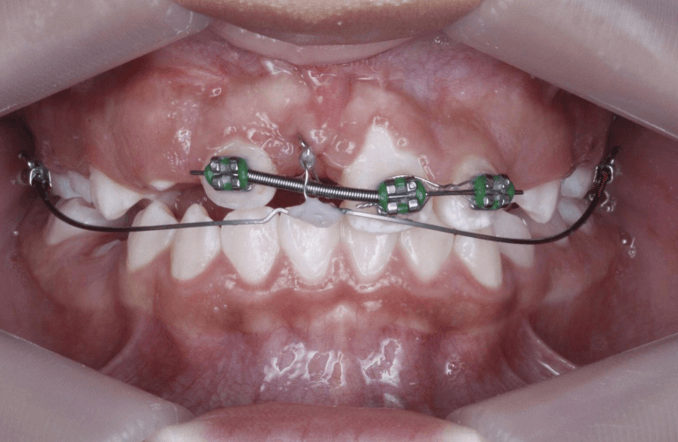

Paciente de 10 años de edad, sexo femenino, acude a consulta para evaluación ortodóntica durante un tratamiento de ortodoncia iniciado en otra consulta, en antecedentes patológicos previos refiere extracción de odontoma compuesto en sector antero-superior del cuadrante 1. Se realiza registro fotográfico (Fig 1) donde se observa presencia de una inserción papilar del frenillo labial, ausencia clínica del incisivo central 1.1 junto con escaneo intraoral en donde se evidencia el estado del tratamiento ortodóntico (Fig 2, 3, 4)

Fig 1-4. Fotografía intraoral de frente y capturas de pantalla de escaneo intraoral vista oclusal, lateral derecha e izquierda